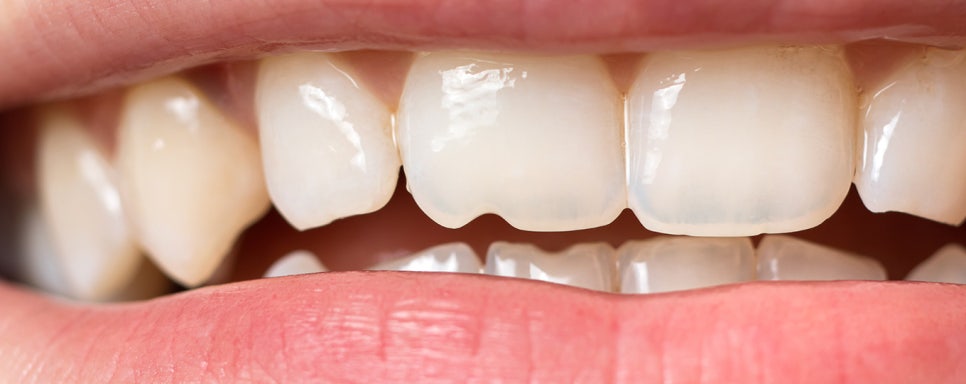

뉴티스 치아성형: 법랑질 다듬기

뉴티스 치아성형은 미세한 치아 깨짐이나

길이가 다른 치아 절단면을 다듬어

가지런하게 만드는 데 목적이 있습니다.

미세한 형태 개선으로

손상없이

치아 가장 겉면에 위치하는

단단한 법랑질을 미세하게 다듬기 때문에

치아 손상이 없고

원하는 형태로 치아를 개선할 수 있습니다.

✅마취와 통증 無

✅ 치아손상 無

✅ 간단하게 당일 시술